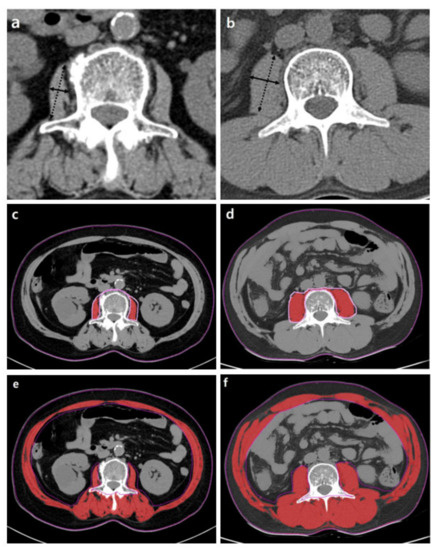

With advances in MRI techniques, the assessment of the chemical composition of tissue has also become possible. MR spectroscopy (MRS) is a representative MR technique that assesses the chemical composition of tissue [51,52]. DIXON-based MRI is a recent MRI technique challenging MRS by using a chemical shift to enable the selective reconstruction of fat signal- and water signal-only images [53,54]. Quantitative analysis using DIXON-based MRI showed an excellent correlation in MRS, which outperformed visual assessment in the detection of muscle fat content [55]. These fat quantification MRI techniques could be applied to the evaluation of sarcopenia in terms of muscle quality assessments in patients with chronic liver disease (Figure 4).

Figure 4.

Example MR images (fat fraction) of cross-section of the spinal muscles at the Superior Mesenteric Artery level in two patients with low fatty degeneration (a) and high fatty degeneration (b). (a) The area and fat fraction of the left spinal muscle were 3150 mm2 and 10.3%. (b) The area and fat fraction of the left spinal muscle were 1394 mm2 and 44.3%. An axial three-dimensional multi-echo-modified Dixon gradient echo sequence was used for the MRI. Imaging parameters for the sequence were as follows: six Echo Time (TE)s (first TE shortest automatic (0.9–1.2ms), delta TE 0.8–1.01ms); Repetition Time (TR) shortest automatic (5.8–6.3 ms); flip angle =3; field of view = 35 × 35 cm2; 3 mm slice thickness with no gap; matrix size = 300 × 300; number of slices = 60; scan time = 14.1 s; parallel imaging SENSE factor = 2; number of signal average = 1. The sequence automatically produces water, fat, fat fraction, R2*, and T2* maps.